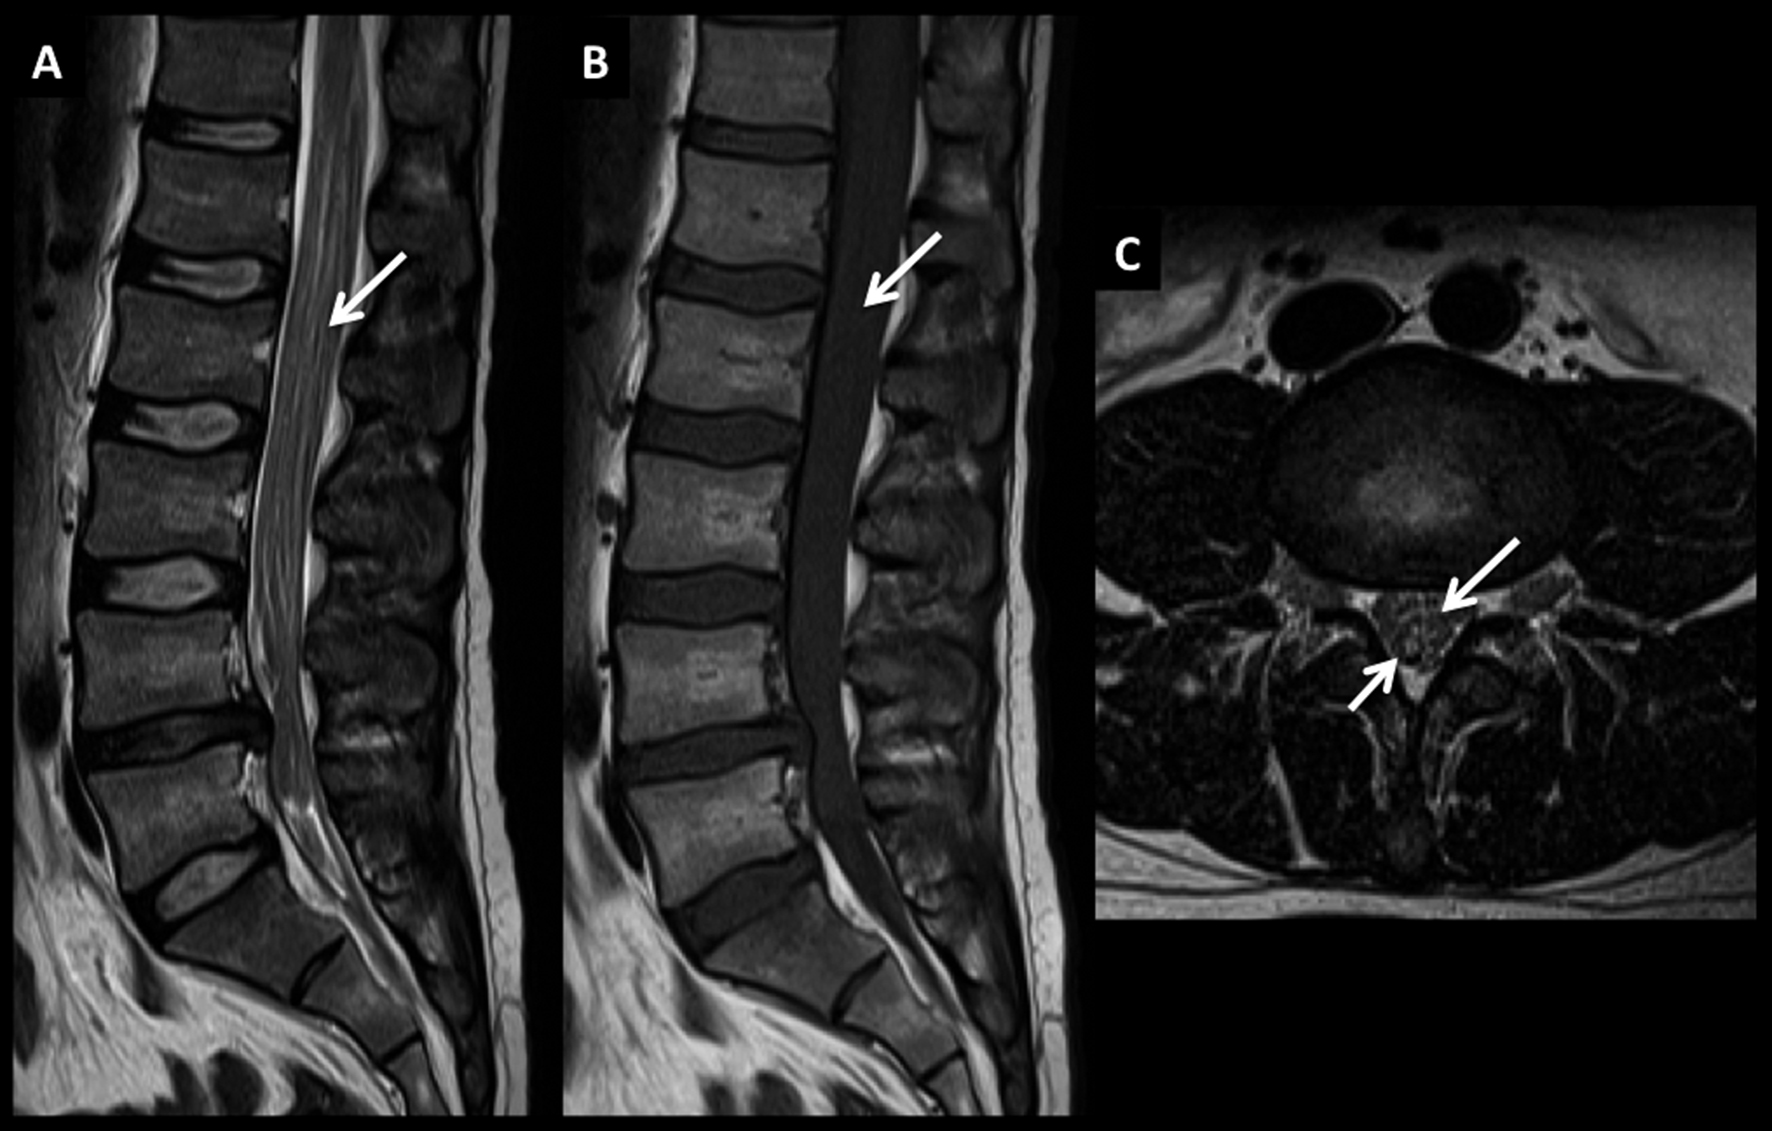

LNH, infiltración de cola de caballo, compromiso leptomeníngeo secundario.

Paciente joven con LNH y síndrome radicular asociado. En el estudio de estadificación se encuentra un patrón de infiltración de las raíces de la cola de caballo y se confirma el diagnóstico por estudio citológico del líquido céfalo raquídeo.

Este tipo de patrón se caracteriza por raíces nerviosas engrosadas que luego de administrar medio de contraste (D a F) presentan intenso realce.

El proceso infiltrativo rodea al cono medular (flecha discontínua) y puede contribuir a la clínica del paciente.